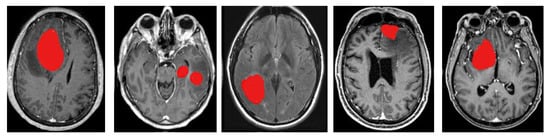

4.2. Segmentation

Canny Algorithm